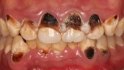

▲牙医表示,要正确刷牙才能真的清洁口腔

现代人重视牙齿健康,但对于刷牙仍有错误迷思,牙医表示,要正确刷牙才能真的清洁口腔,一般民众有4大错误的刷牙观念,例如用力刷比较干净、饭后赶快去刷牙、刷牙就是刷牙齿等,事实上,刷牙太用力会导致牙龈受伤,且磨损牙齿表面,而饭后刷牙可能会因食物属酸性物质,而害珐琅质受损。